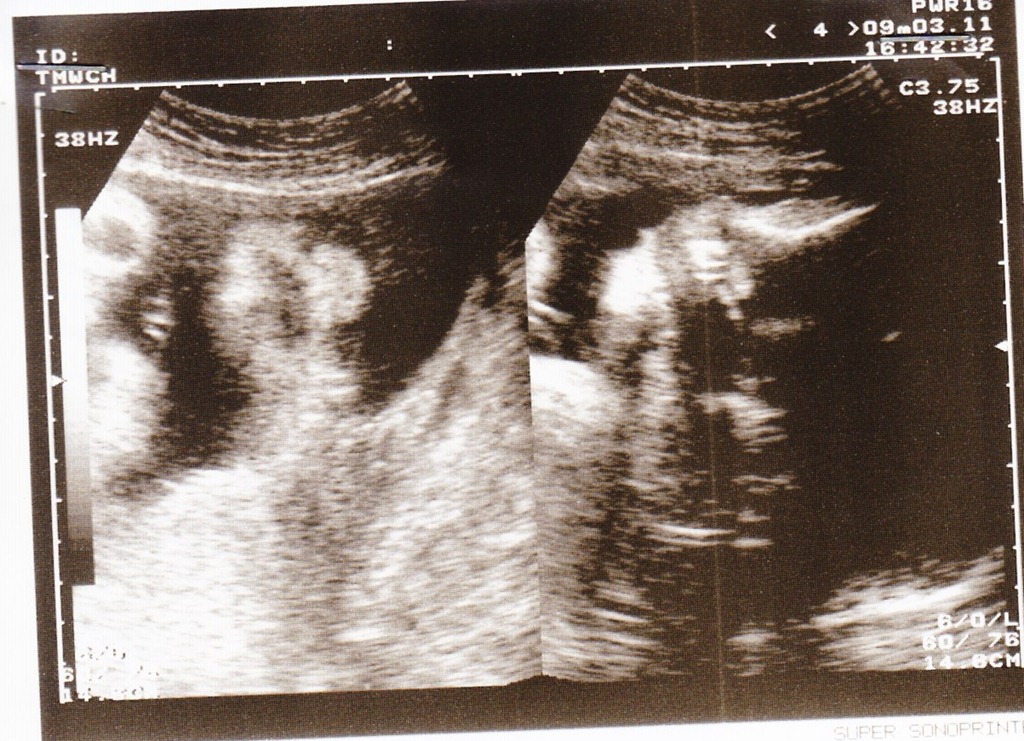

接著這周我們還去做了頸部透明帶的篩檢,此時的我身長6.1公分,雙手、雙腳、手指骨都可以看見,小手在羊水中不停的揮動著,腳則是交叉盤腿、伸直、彎曲等姿勢都有,變來變去的~下次再去看醫生伯伯,就可以知道頸部透明帶篩檢的結果了~